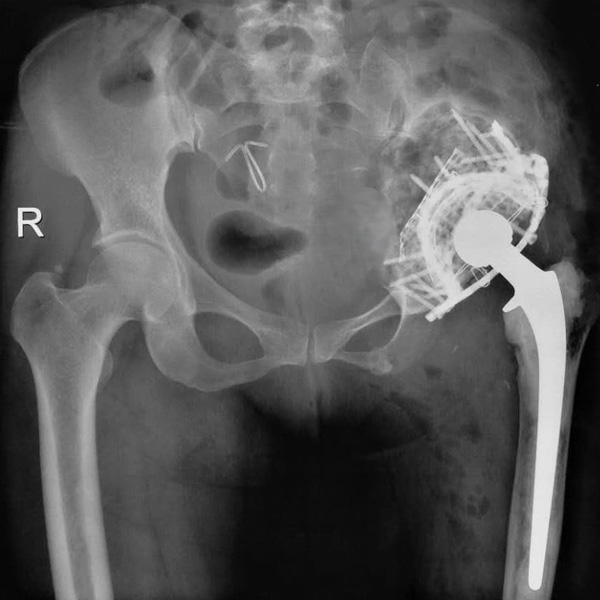

• 髖關節翻修髖關節翻修手術后手術前

髖關節翻修

患者蘇某,女性,11年前因“左髖關節屈曲攣縮畸形”行左側人工全髖關節置換,近來感覺左髖關節疼痛,不敢行走,經“攜生醫療平臺”就診于哈......